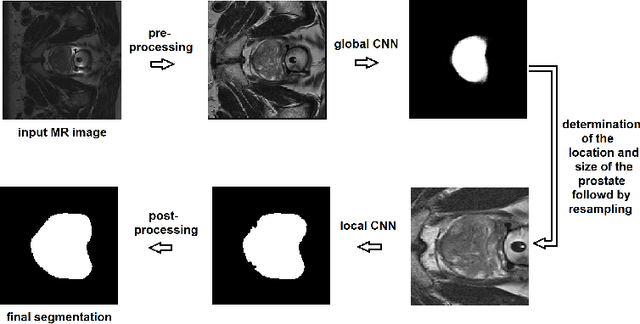

Abstract:We propose a novel automatic method for accurate segmentation of the prostate in T2-weighted magnetic resonance imaging (MRI). Our method is based on convolutional neural networks (CNNs). Because of the large variability in the shape, size, and appearance of the prostate and the scarcity of annotated training data, we suggest training two separate CNNs. A global CNN will determine a prostate bounding box, which is then resampled and sent to a local CNN for accurate delineation of the prostate boundary. This way, the local CNN can effectively learn to segment the fine details that distinguish the prostate from the surrounding tissue using the small amount of available training data. To fully exploit the training data, we synthesize additional data by deforming the training images and segmentations using a learned shape model. We apply the proposed method on the PROMISE12 challenge dataset and achieve state of the art results. Our proposed method generates accurate, smooth, and artifact-free segmentations. On the test images, we achieve an average Dice score of 90.6 with a small standard deviation of 2.2, which is superior to all previous methods. Our two-step segmentation approach and data augmentation strategy may be highly effective in segmentation of other organs from small amounts of annotated medical images.